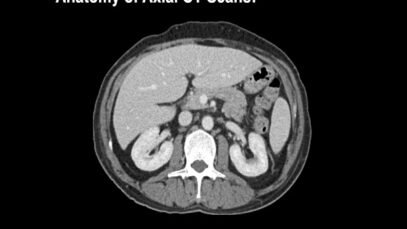

Normal Abdominal _ Pelvic CT Anatomy_ Algorithm – Radiology

Structure and Function The abdomen consists of the organs necessary for digestion. These include the stomach, pancreas, liver, gallbladder and small and large intestines. The abdomen also contains the kidneys and spleen. Connecting tissues called the mesentery, hold these organs together. The mesentery also allows these organs to move relative to one another and expand. […]